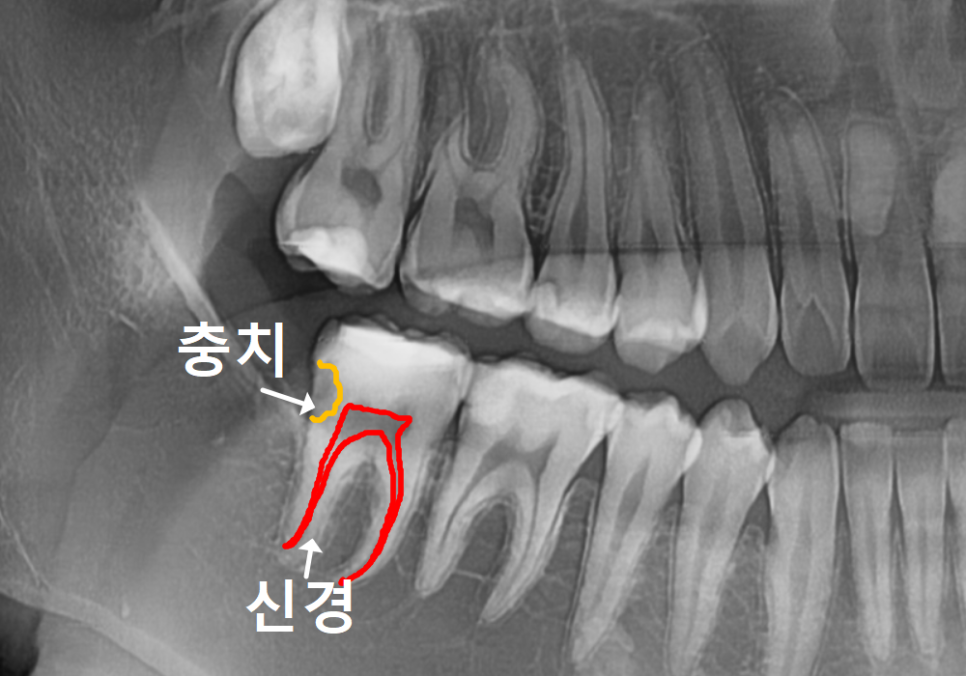

충치를 제거해 보니 생각보다 충치가 깊고,

신경과 아주 아슬아슬하게 맞닿아 있었습니다.

저희 치과의 철학이 '자연 치아 살리기'인 만큼,

"어떻게든 신경을 살려볼 수 없을까?"

고민이 깊었죠.

그래서 바로 신경치료를 하기보다는

신경 보호를 돕는 약재를 먼저 채워 넣었습니다.

230116

치아는 스스로를 보호하는 힘이 있어서,

약재의 도움을 받으면 신경 위로

새로운 치아 조직(상아질)을

만들어내기도 하거든요.

치아 스스로 '굳은살'을 만들어

신경을 보호하도록 시간을 두고 기다려 본 것이죠.